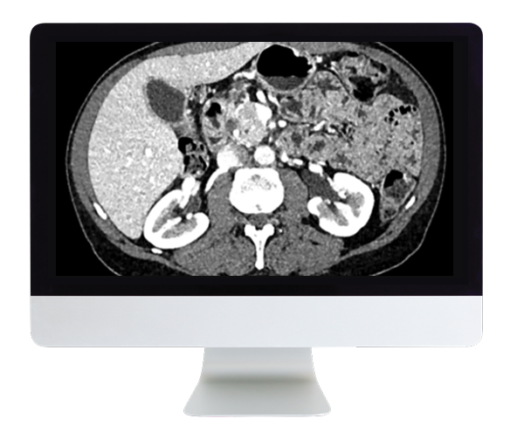

ARRS Gastrointestinal Imaging Online Course 2019 (CME VIDEOS) This Online Course covers key gastrointestinal findings—pearls and pitfalls in liver, biliary, bowel, and pancreatic imaging.